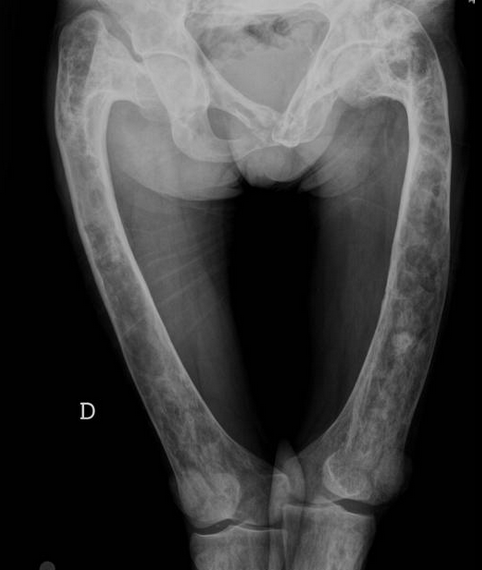

Pagets Disease

• Expansion of bone with thickened trabecula

• Multiple lesions

• Pelvis most commonly affected

• Almost never in fibula

• Blade of grass —> pointed appearance of lesion within the bone

• Secondary osteosarcoma can occur —> very bad

• Shephard crook deformity of femur